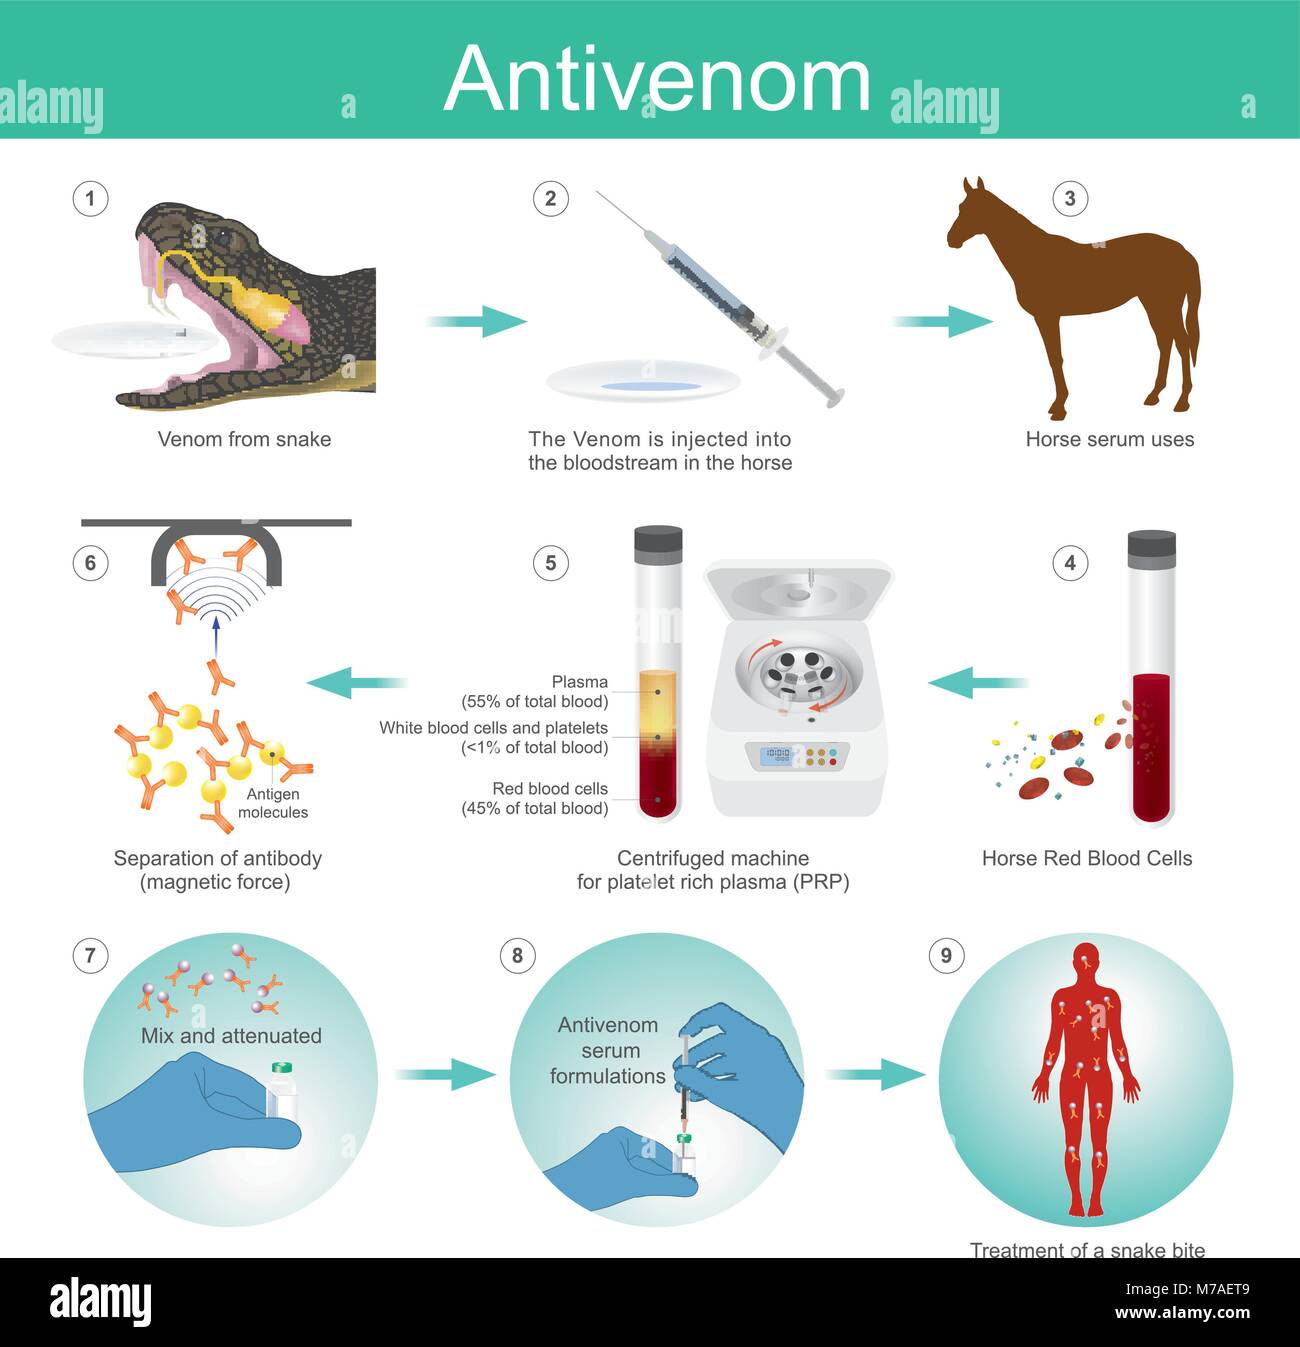

Anti venom è un farmaco costituito da anticorpi dal sangue rosso cavallo che è usato per trattare alcuni morsi velenosi. Illustrazione Vettorialehttps://www.alamy.it/image-license-details/?v=1https://www.alamy.it/foto-immagine-anti-venom-e-un-farmaco-costituito-da-anticorpi-dal-sangue-rosso-cavallo-che-e-usato-per-trattare-alcuni-morsi-velenosi-176637449.html

Anti venom è un farmaco costituito da anticorpi dal sangue rosso cavallo che è usato per trattare alcuni morsi velenosi. Illustrazione Vettorialehttps://www.alamy.it/image-license-details/?v=1https://www.alamy.it/foto-immagine-anti-venom-e-un-farmaco-costituito-da-anticorpi-dal-sangue-rosso-cavallo-che-e-usato-per-trattare-alcuni-morsi-velenosi-176637449.htmlRFM7AET9–Anti venom è un farmaco costituito da anticorpi dal sangue rosso cavallo che è usato per trattare alcuni morsi velenosi.